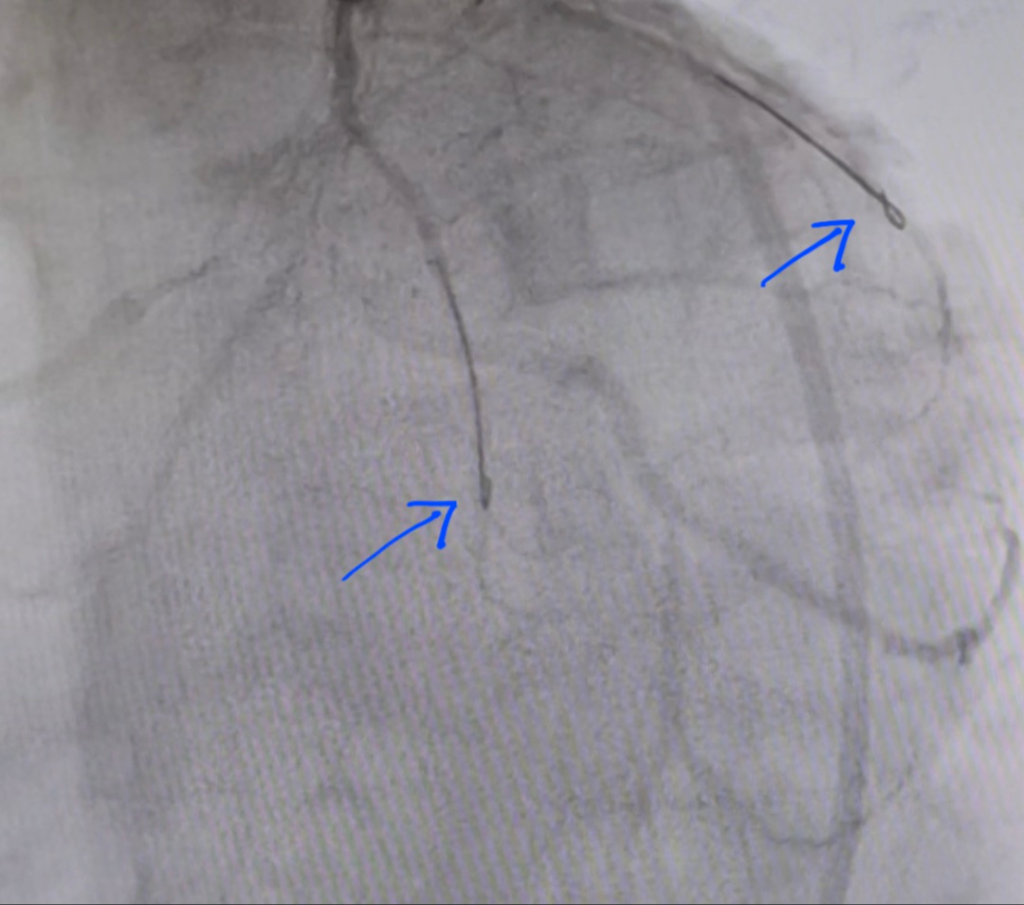

가족이 스텐트 시술을 받았는데, 받아온 시술영상에 고리 같은게 있는데 무엇일까요?

1) 스텐트시술에 사용한 해당 인공물(파란색 화살표)이 중간에 끊어져서 회수(제거)가 안될 수도 있는지

2) 시술이 끝나면 반드시 제거가 되어야 하는건지 궁금합니다~

홍성의료원

1. 가이드와이어가 보이는 것입니다, 중간에 끊어져서 회수가 안 될 수 있긴 하지만 그럴 경우 병원에서 먼저 인지하여서 수술적으로라도 제거를 합니다. 현실적으로 그럴 가능성은 전혀 없다고 볼 수 있습니다.

2. 시술이 끝나면 당연히 제거를 합니다.

올리신 사진만으로는 제한적이나 스테스 삽입을 위한 가이드 와이어 같아보이며 이럴 경우 역활이 끝난 뒤 회수 됩니다.

시술과정에서 스텐트를 삽입하기 위해서는 가이드 와이어 등을 넣게 되는데 그 가이드 와이어 등으로 보여집니다.

시술후에는 다 제거가 되었을 것입니다.